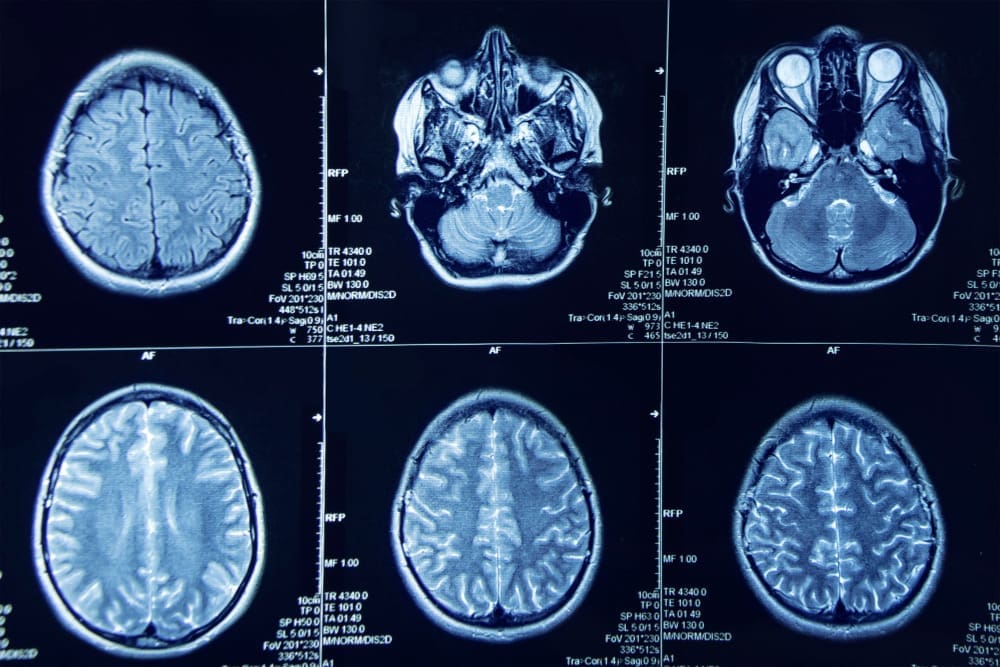

There are mainly two kinds of strokes: ischemic and hemorrhagic. Ischemic strokes happen when a blood vessel in the brain gets blocked. Hemorrhagic strokes occur when a blood vessel bursts and bleeds into the brain.